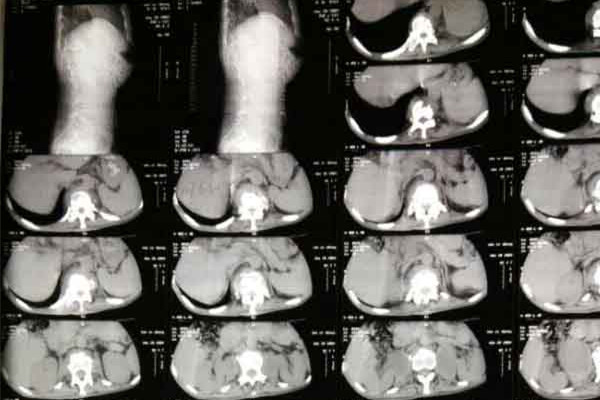

首先脊柱结核,为肺外结核的一种,也是骨关节结核中最常见的类型。绝大多数脊柱结核的病人病原菌来自肺结核。当结核菌随血液散播至脊柱时,就有可能导致脊柱结核的发生。

与开放性肺结核区别在于脊柱骨结核一般不具备传染性,但仍然需要积极治疗,目前临床上常见的主要是抗结核药物治疗,治疗过程中严格遵循用药原则,全程规律的用药,不可擅自停药或漏用药物。此外还要用心监测药物治疗带来的不良反应,好及时咨询医生对症处理。此外对于形成脓肿、脊柱畸形、骨质破坏影响脊柱稳定、病灶压迫神经等情况,可以采取手术治疗。手术治疗后仍需要继续抗结核药物治疗。